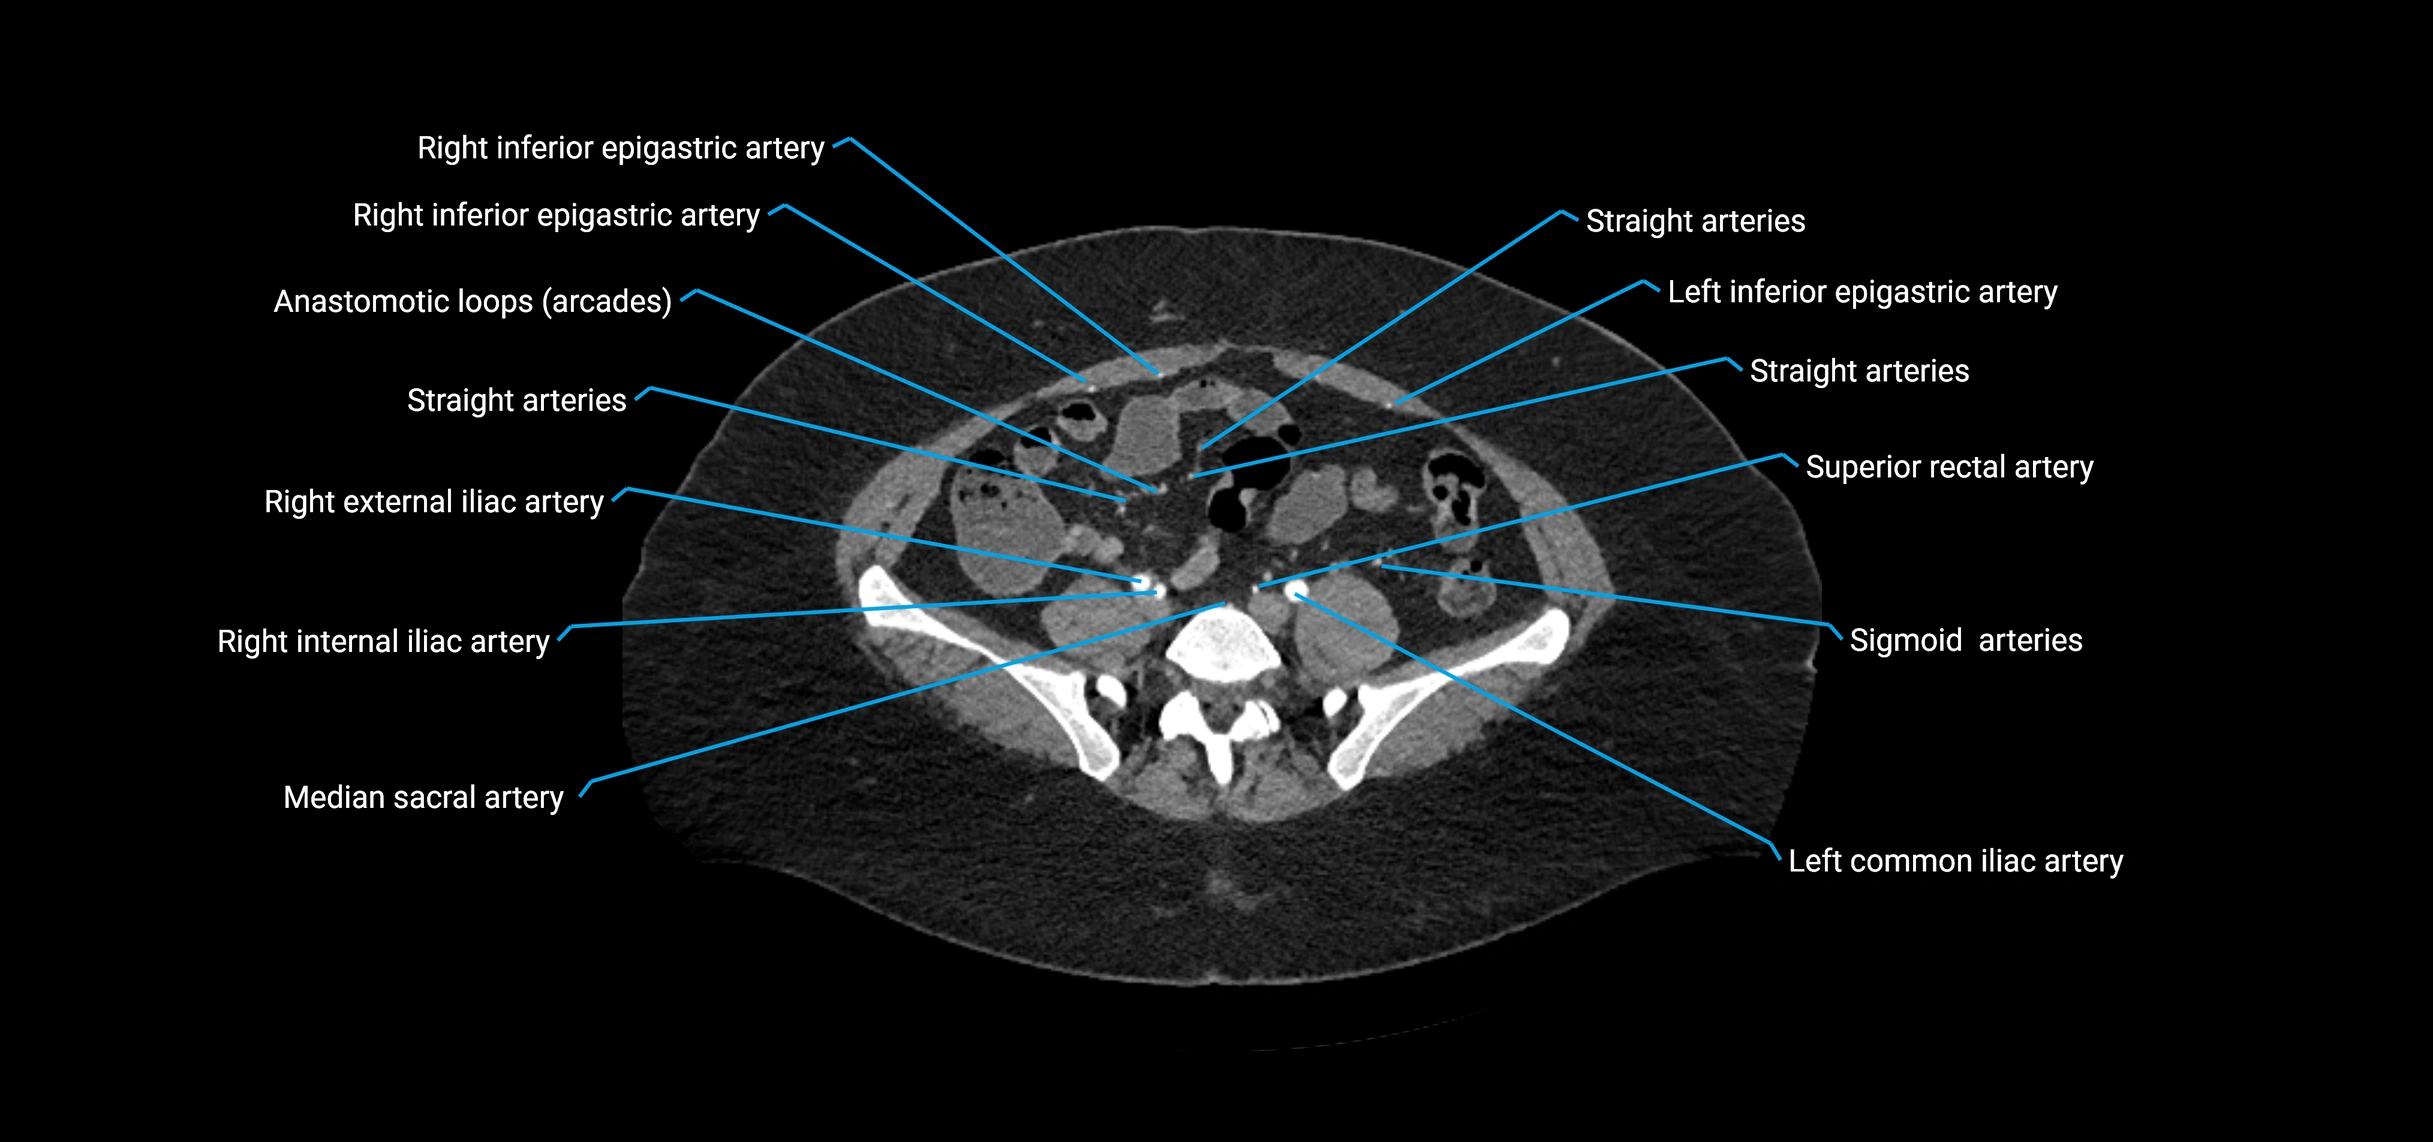

Contrast-enhanced CT (CTA):

• Gold standard for abdominal aortic imaging

• Provides excellent detail of lumen, wall, aneurysm, thrombus, and branch vessels

• Multiplanar and 3D reconstructions help in aneurysm measurement, stent graft planning, and dissection evaluation

• Detects acute rupture, traumatic injury, or occlusion with high sensitivity